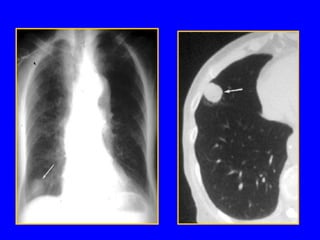

Padrões Radiológicos

Nódulo Pulmonar

• < 3cm diâmetro

• Redondo ou oval

• Homogênea

• Limites bem

definidos

• Único ou múltiplo

• Presença de

calcificações

cavitações